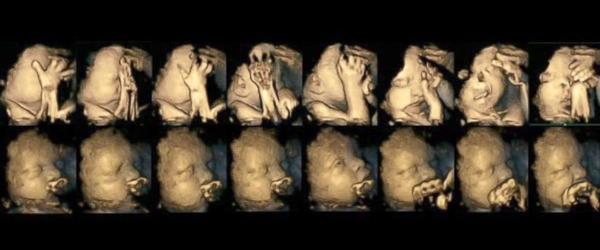

@jitulinkaaa tohle jsou ultrazvuky miminek, a rozdíl mezi miminkem nekuřačky, a kuřačky po tom co si zakouřila jen 1 cigaretu je markantní... !! miminko se dusí !! ...